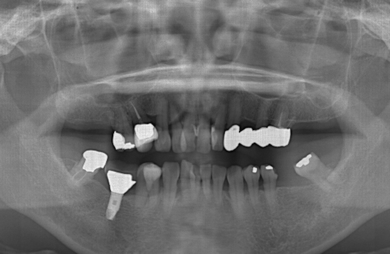

インプラント+ソケットリフト

性別/年齢

女性 / 52歳

主訴

以前抜歯した部分に義歯かインプラントかブリッジを入れて欲しい。左上の歯のすいている所をセラミックでカバーしたい。

治療方針

骨がしっかりとあるので、通常のインプラント治療で歯の無い部分に歯を作る。

治療内容

インプラント1本、ハイブリッドセラミック2本

治療部位

4

5

総治療費

434,500円

治療期間

海外から0.7ヶ月

治療前

治療後